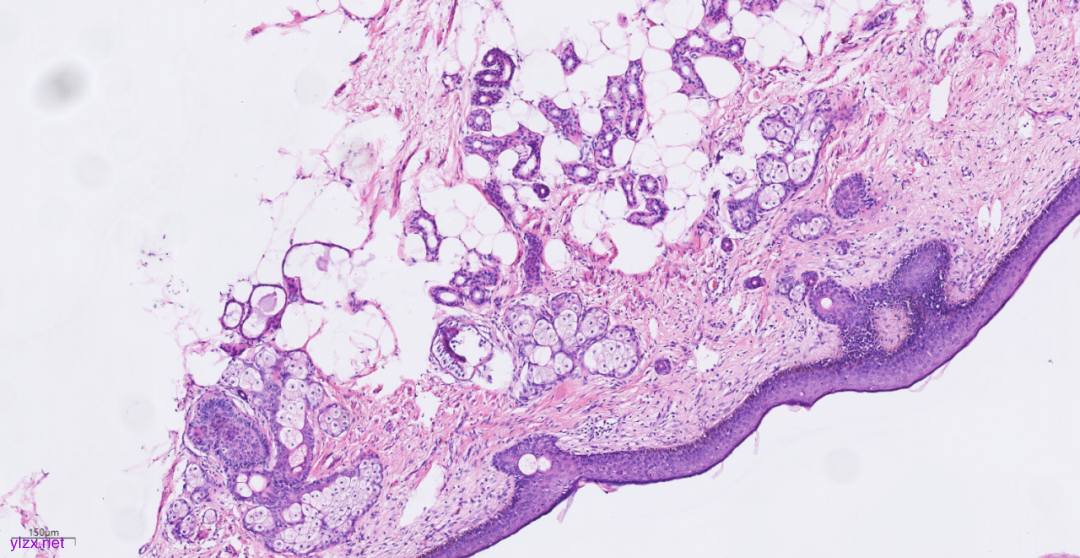

3.2镜下观(图3-图9):

低倍镜下可见卵巢肿物呈囊,中倍镜下,囊壁见分化成熟的多胚层成分,成熟型囊性畸胎瘤区域可见皮肤(正常鳞状上皮及其表明角化物)及其附属器成分(皮脂腺、汗腺及毛囊),局部囊壁表面可见由正常鳞状上皮-原位癌-鳞状细胞癌逐渐过渡;在鳞状细胞癌区域,囊壁增生的纤维结缔组织中可见肿瘤细胞呈巢状向下浸润性生长,也向囊腔内乳头状生长,局部癌巢中央可见角化珠及坏死;高倍镜下,鳞癌成分肿瘤细胞大小不等,细胞排列紊乱,细胞中-重度异型,核大深染,略呈空泡状,核仁明显,核分裂象易见,伴角化珠形成。

图3 低倍镜下可见卵巢肿物呈囊。

图4 中倍镜下,成熟型囊性畸胎瘤区域可见正常鳞状上皮、皮脂腺、汗腺及毛囊。

图5 局部囊壁表面可见由正常鳞状上皮-原位癌-鳞状细胞癌逐渐过渡。

图6 在SCC区域,癌巢向下浸润性生长,也向囊腔内乳头状生长。